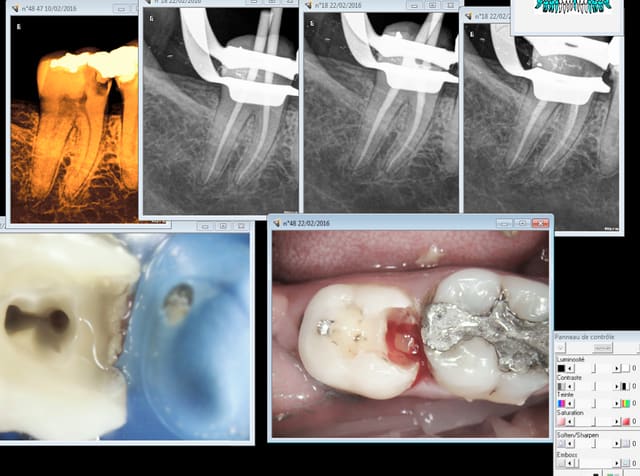

Imaginons qu'on fasse une pano à la place de clichés rétroalvéolaires.

Lors de la séance suivante, on décide de faire une endo.

On réalise au moins trois clichés rétroalvéolaires , dont une pré, une per et une finale.

D'après toi, à quelle cotation a t-on droit ?

Un HBQK303 ou un HBQK040 ?

23/02/2016 à 11h23

Ta pano ne peut etre réalisée qu'en présence de signes d'appels. J'en conclue que c'est soit une pulpite soit un 4 ième. Mais vas tu coter une C ou un pano ? -)

Je te laisse en tirer les conclusions. -)

Hbqk 303.